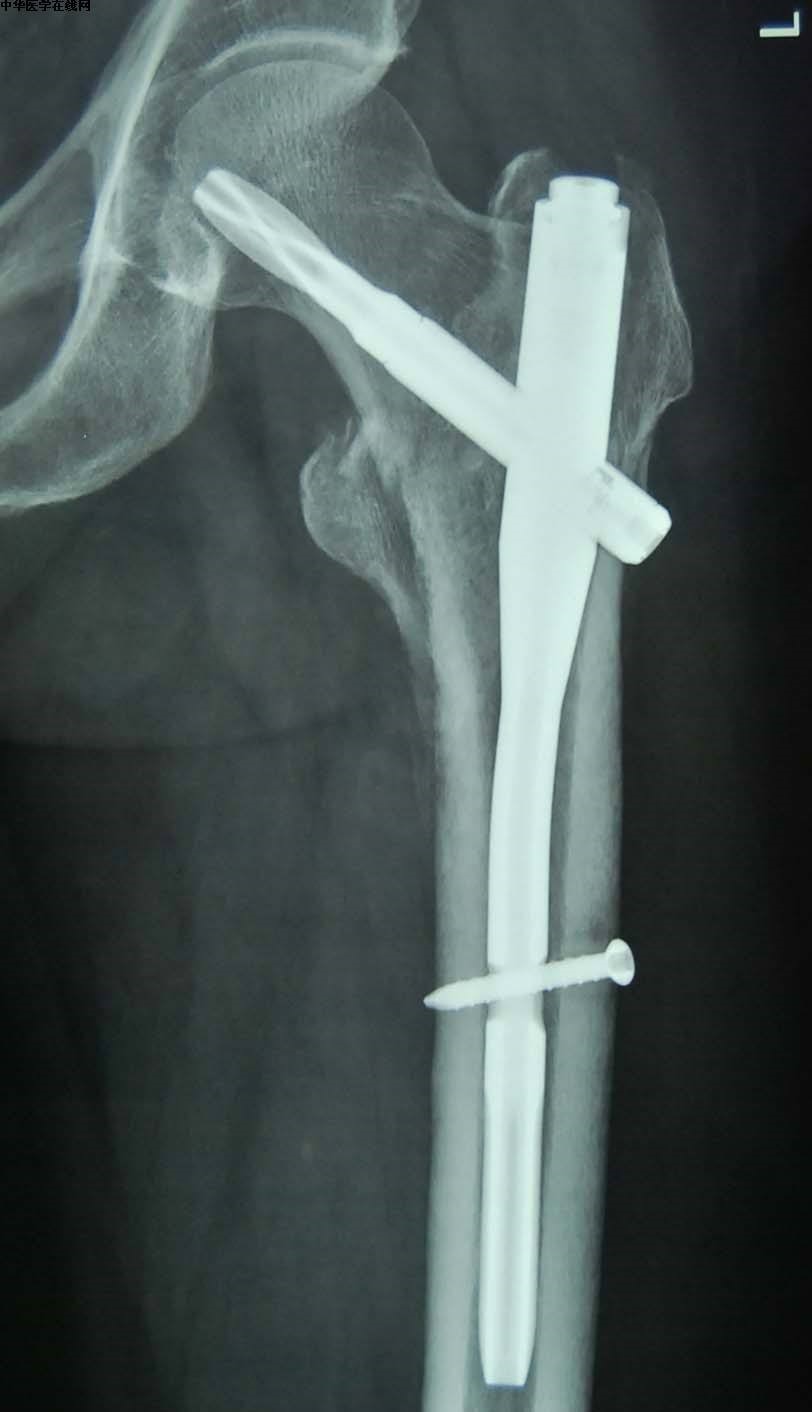

三、股骨粗隆间骨折

保守治疗风险大,极可能引发一系列并发症,如骨折移位、褥疮、肺炎、下肢血栓等,建议行手术复位内固定治疗,手术后尽早减轻疼痛,早期进行功能锻炼,避免长期卧床。并发症如下图: